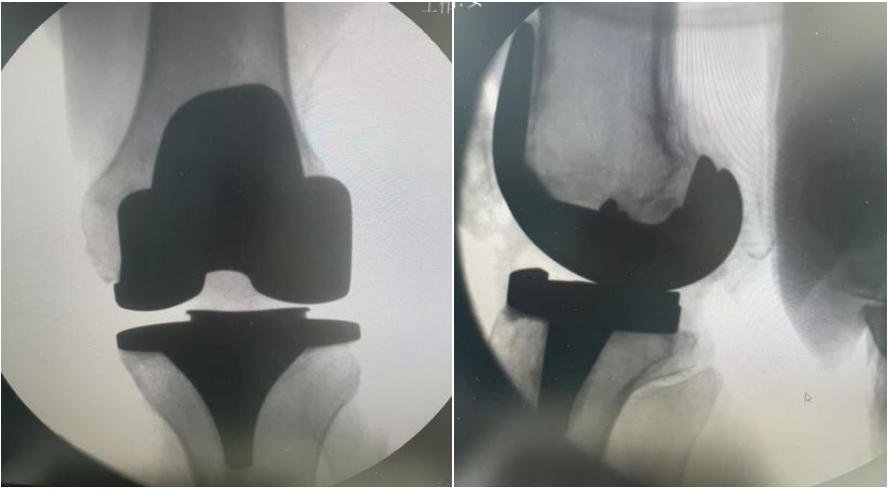

经过充分的术前准备,在椎管内麻醉下,手术团队为患者施行了「左侧人工全膝关节置换术」。手术过程顺利,出血少,患者安返病房。在骨伤科医护团队的精心照护和康复师的指导下, 术后第二天,她已能稳稳站立,并在助行器帮助下迈出步伐。「没想到这么快就能走,感觉轻松多了!」郭阿姨和家属对治疗效果非常满意。

人工膝关节置换术是治疗晚期膝关节病变的有效方式,其优势显著,它能有效缓解各种原因引起的膝关节病变导致的顽固性疼痛、活动受限,且经系统保守治疗无效的老年病人,术后多数患者疼痛明显减轻甚至消失,大大提高生活舒适度。同时,显著改善关节功能,让患者恢复正常行走、上下楼梯等活动能力,提升生活自理与社交参与度。长期来看,可矫正关节畸形,如膝内翻、膝外翻等,改善下肢力线,降低因关节畸形对其他部位造成的不良影响,提高生活质量并减少家庭与社会的医疗负担,是疗效确切、技术成熟的外科手术,